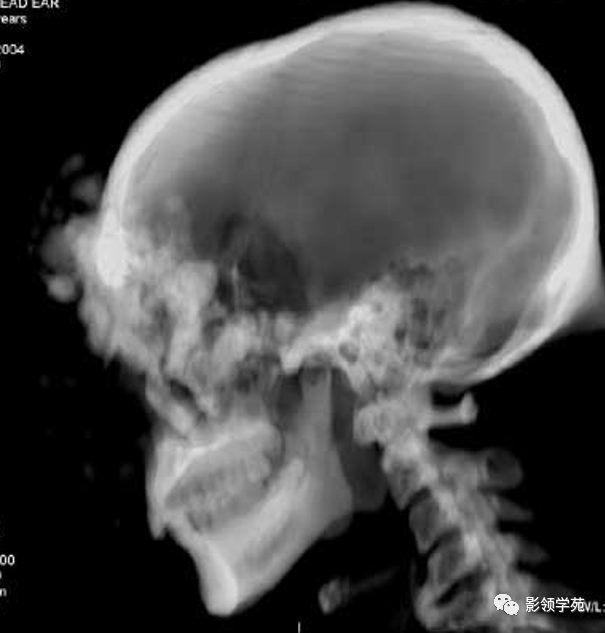

CT诊断:甲状腺癌双肺多发转移